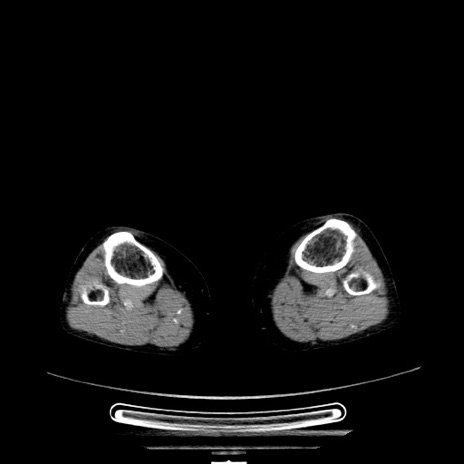

【症例】70歳代女性

【主訴】お腹が張る

【現病歴】1週間くらい前から腹部膨満の自覚あり。昨日夜から増悪したため、本日救急外来受診。

【身体所見】意識清明、BT 36.5℃、BP 165/106mmHg、HR 80bpm、SpO2 98%、腹部:膨満、軟、自発痛・圧痛なし、触診にて不快感あり、腸蠕動音:減弱

【データ】WBC 12600、CRP 1.04